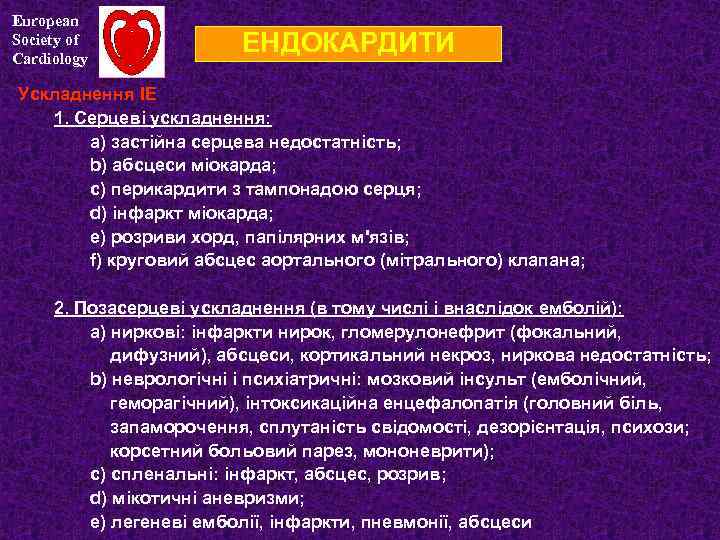

European Society of Cardiology ЕНДОКАРДИТИ Ускладнення ІЕ 1. Серцеві ускладнення: а) застійна серцева недостатність; b) абсцеси міокарда; с) перикардити з тампонадою серця; d) інфаркт міокарда; е) розриви хорд, папілярних м'язів; f) круговий абсцес аортального (мітрального) клапана; 2. Позасерцеві ускладнення (в тому числі і внаслідок емболій): а) ниркові: інфаркти нирок, гломерулонефрит (фокальний, дифузний), абсцеси, кортикальний некроз, ниркова недостатність; b) неврологічні і психіатричні: мозковий інсульт (емболічний, геморагічний), інтоксикаційна енцефалопатія (головний біль, запаморочення, сплутаність свідомості, дезорієнтація, психози; корсетний больовий парез, мононеврити); с) спленальні: інфаркт, абсцес, розрив; d) мікотичні аневризми; е) легеневі емболії, інфаркти, пневмонії, абсцеси